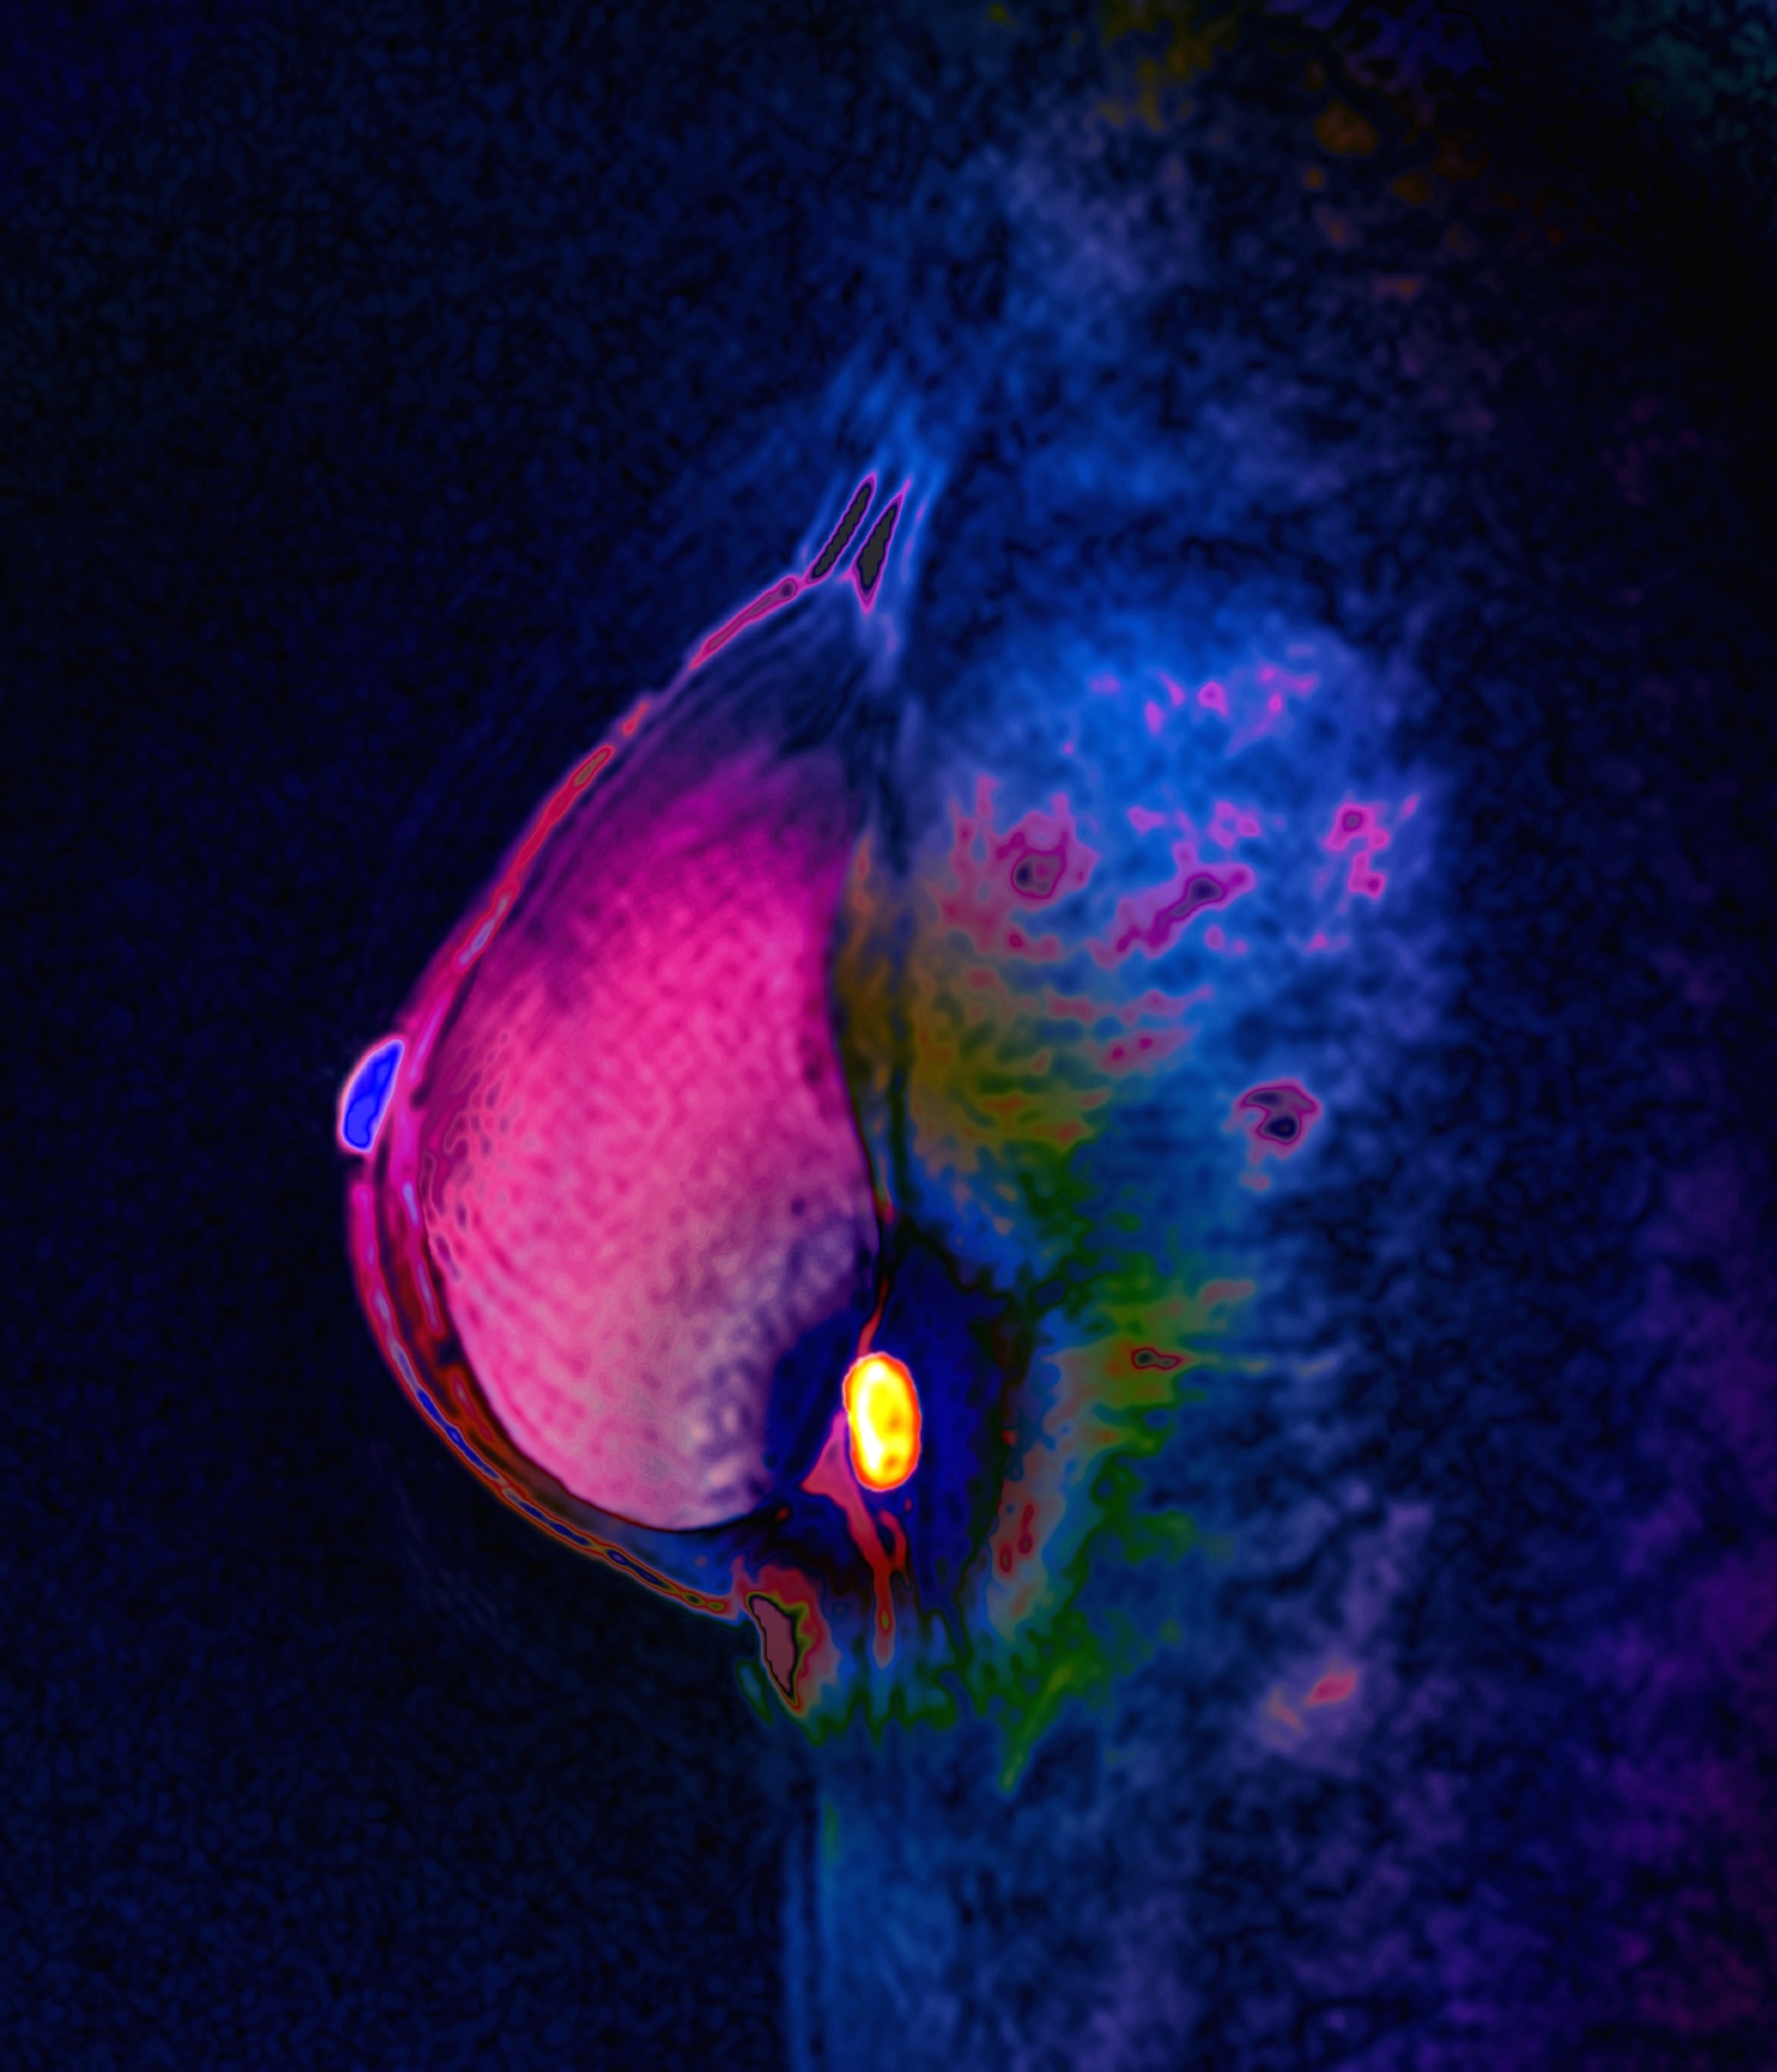

Analysis of thousands of tumors shows that inherited genes determine how a breast tumor develops from its earliest stages.

A woman’s inherited genes are a powerful indicator of what kind of breast cancer she might develop, a recent study reveals.

This type of investigation required lots of data, so Houlihan and Curtis stitched together information from a range of datasets, including tumor cell atlases and cancer registries. Their analysis of over 6,000 breast tumors showed that cells varied in what scientists call their “germline epitope burden,” which could help predict how aggressive a cancer might form.